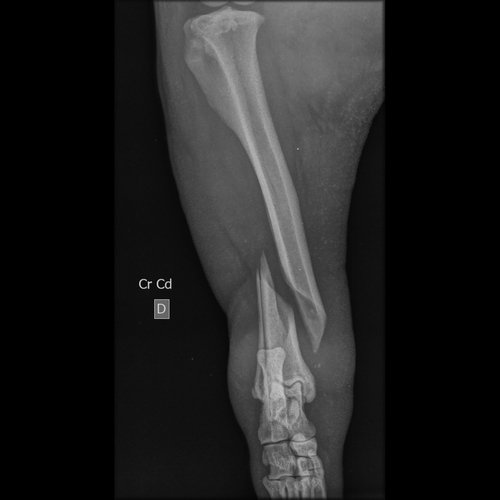

Oi, eu sou a Maria Eduarda, estudante de medicina veterinária e hoje chegou na clínica que eu estou estagiando, um cachorro de rua atropelado, com fratura em femur e tibia e doença do carrapato.